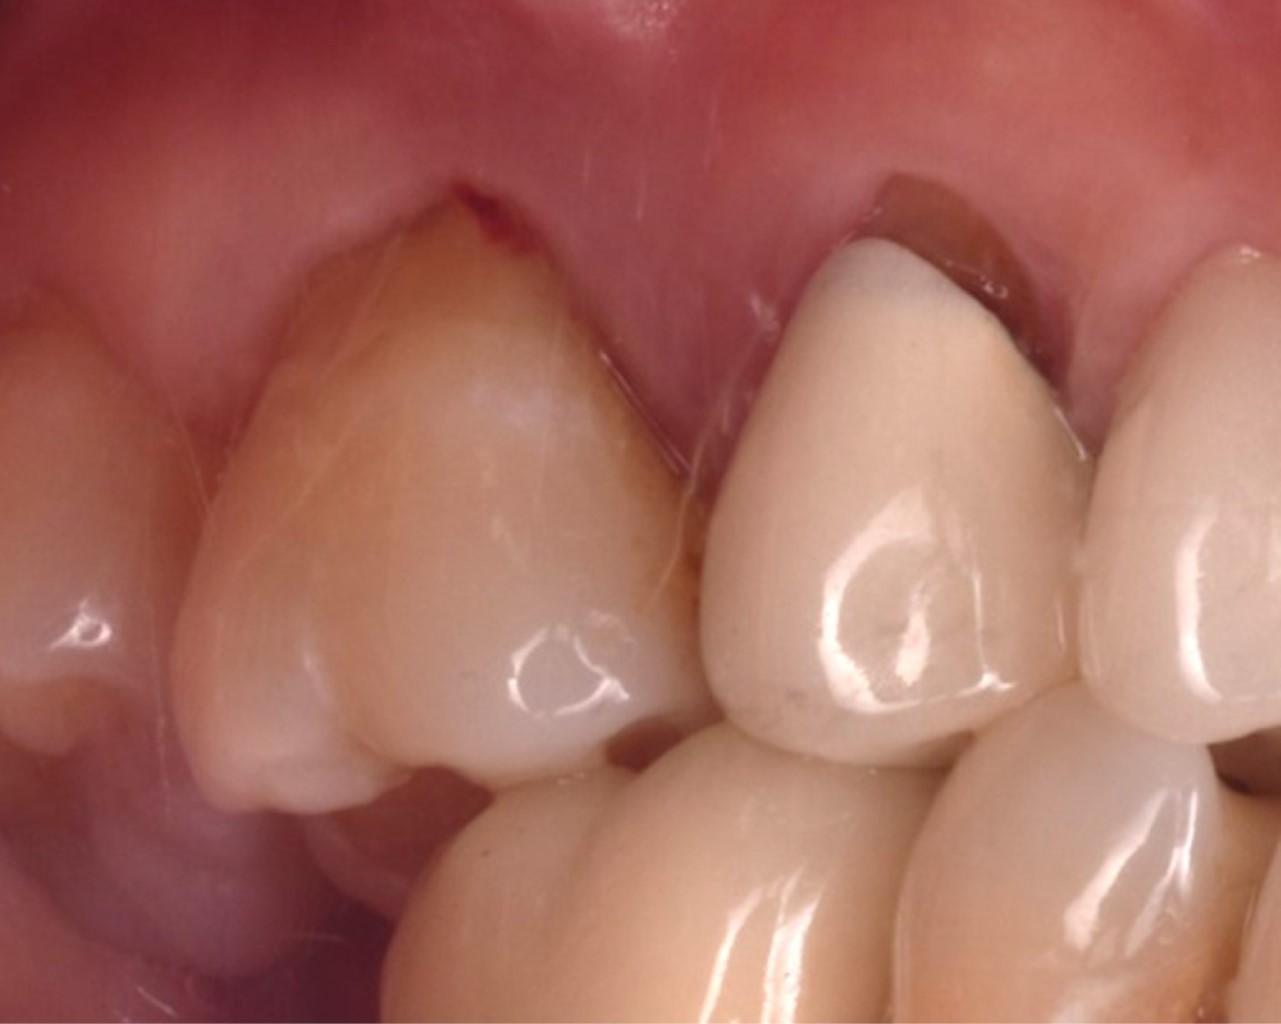

Las proteínas derivadas del esmalte (Emdogain®) se obtienen por medio de la odontogénesis en el periodo de yema de la dentadura porcina; la proteína principal es la amelogenina que presenta una biocompatibilidad con las proteínas del esmalte humano. Los cultivos in vitro han demostrado que Emdogain® al ser agregado a los fibroblastos causa una mejora en la producción de proteínas y colágeno, mineralización y proporciona condiciones favorables a la matriz, proliferación celular, migración, diferenciación y síntesis (Figuras 1, 2, 3, 4, 5 y 6). La capacidad osteogénica se relaciona de manera directa con las proteínas que contiene y esto produce una capacidad osteoinductiva y puede contener factor de crecimiento transformante beta y proteína morfogénica ósea (BMP, por sus siglas en inglés) aunque en menor cantidad.10

Se presenta, en la Especialidad en Periodoncia de la Universidad Autónoma de Baja California (UABC) campus Mexicali, un paciente femenino de 60 años, ASA I, sin antecedentes patológicos, cuyo motivo de consulta es "tengo una bolsa periodontal desde los ocho años". Se realizó una evaluación extraoral en la que se detectó hipertrofia bilateral del músculo masetero, de manera intraoral se observó un fenotipo delgado, presencia de restauraciones desajustadas, desgaste por bruxismo en bordes incisales y cúspides. En el análisis clínico-radiográfico se obtuvo una profundidad de sondaje de 12 mm, efecto intraóseo de una pared según la clasificación de Goldman & Cohen (Figura 7) por vestibular del segundo molar superior derecho, movilidad grado II, con presencia de sangrado, sin sensibilidad. Radiográficamente se observó una zona radiolúcida adyacente a la raíz mesial del segundo molar superior derecho sin presencia de lesión periapical (Figura 8) y, por lo tanto, se estableció el diagnóstico según la "Clasificación de Condiciones y Enfermedades Periodontales y Periimplantarias 2017" como: salud gingival y periodontal en un periodonto reducido, paciente no periodontal, asociado a un trauma oclusal primario;11 y como factor de riesgo se tiene el antecedente de la pérdida prematura del primer molar superior derecho y la mesialización del segundo molar superior derecho.

Figura 1

Figura 2

Figura 3

Figura 4

Figura 5

Figura 6